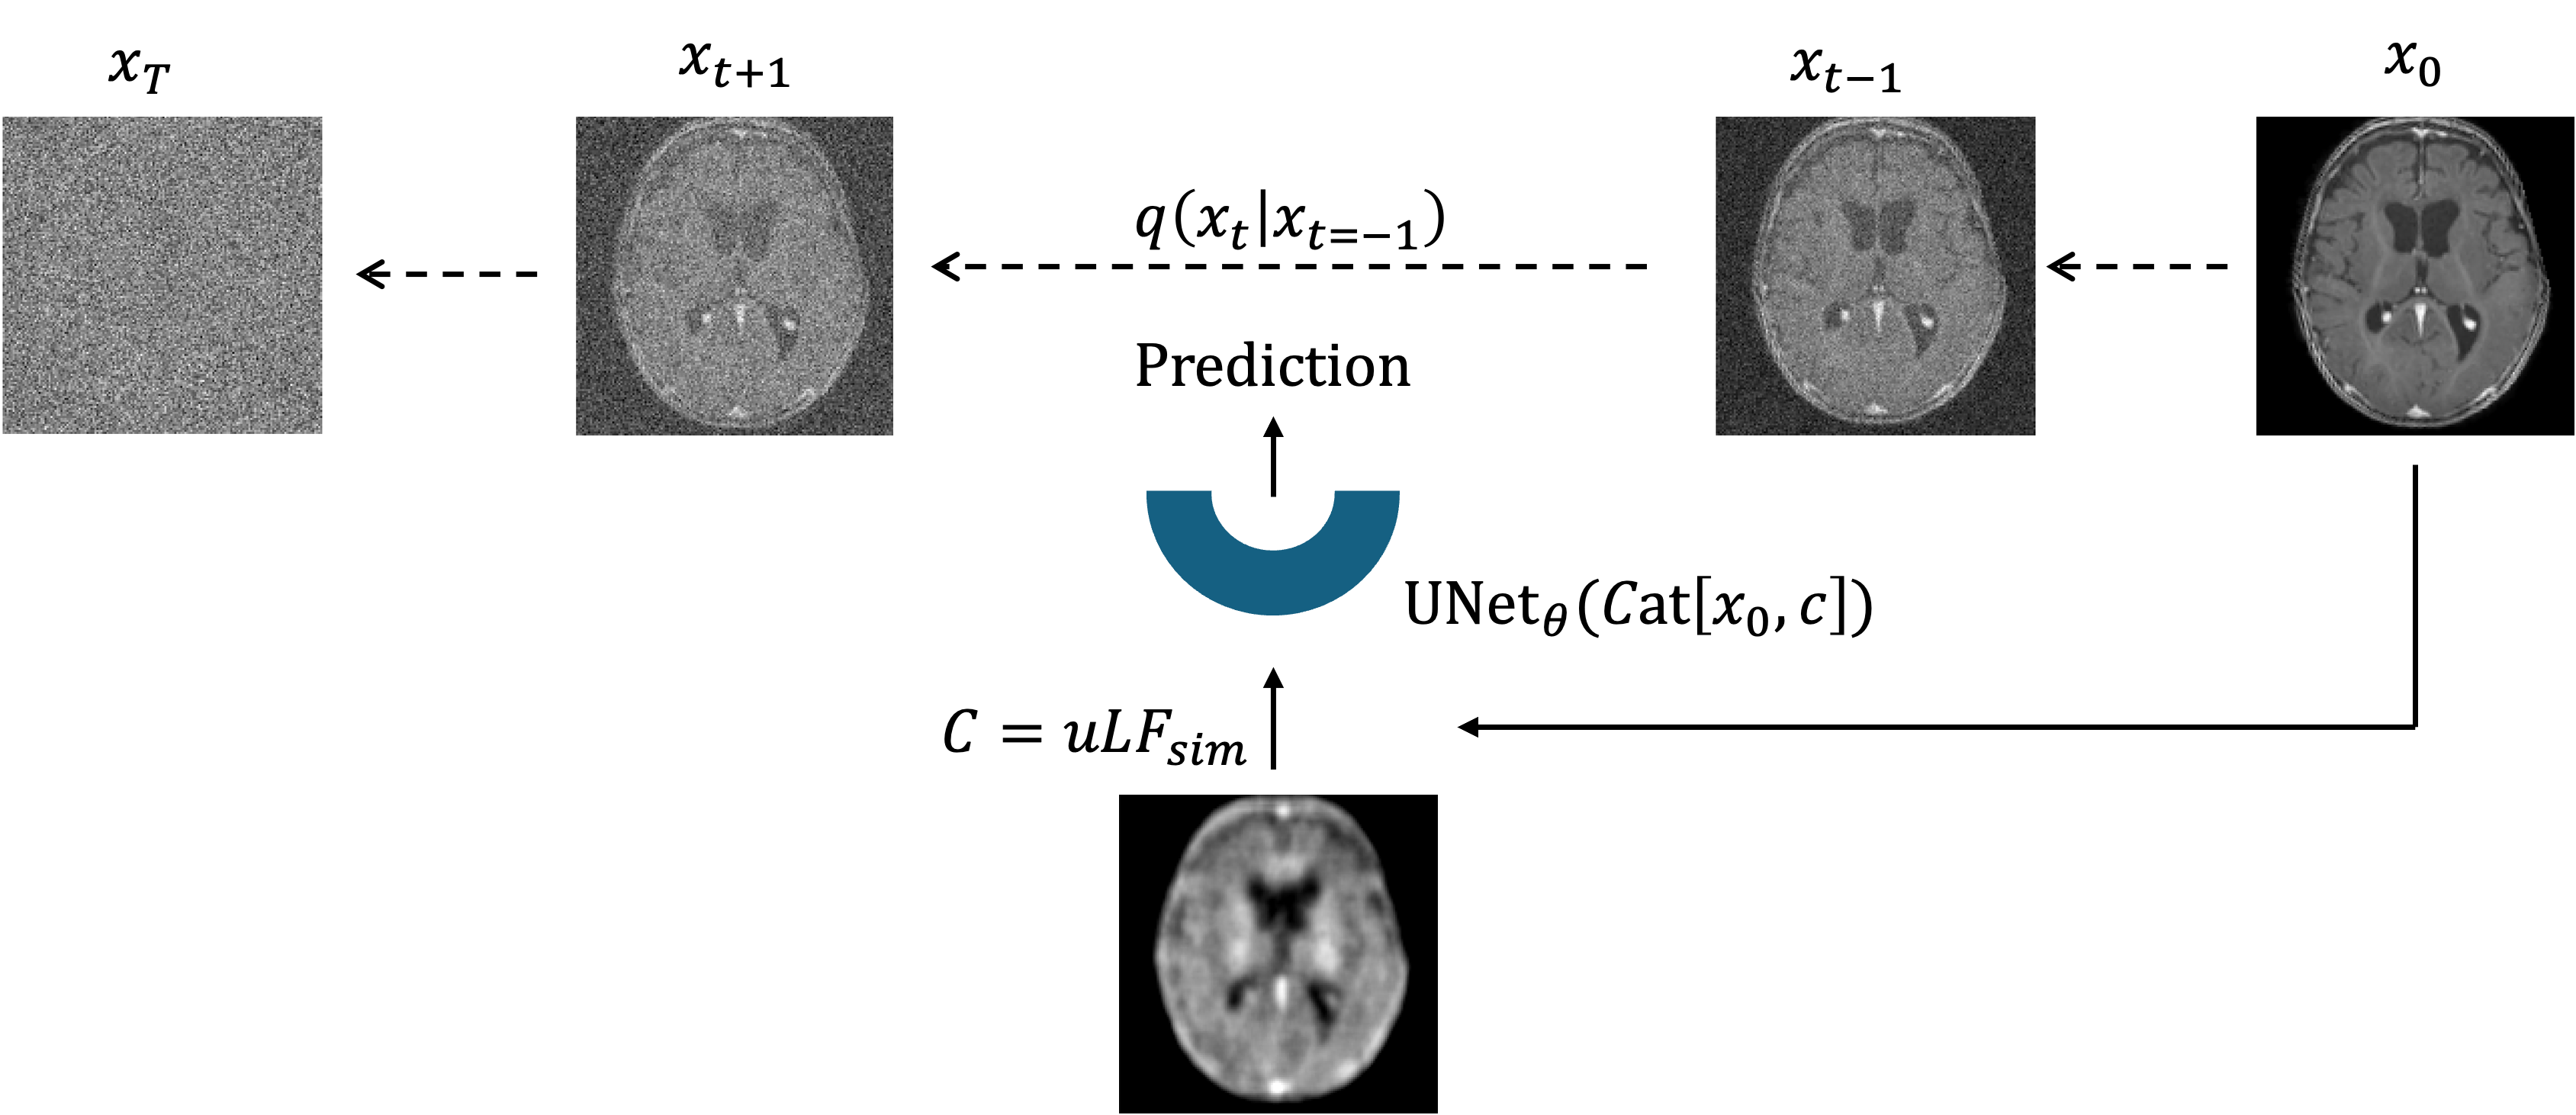

Training: MRIQT is trained as a conditional diffusion model using physics-based uLF simulations to guide anatomically faithful reconstruction from noisy inputs.

Inference: Given a real uLF scan, MRIQT iteratively denoises a noisy initialization while conditioning on the uLF measurement, yielding a high-quality reconstruction.